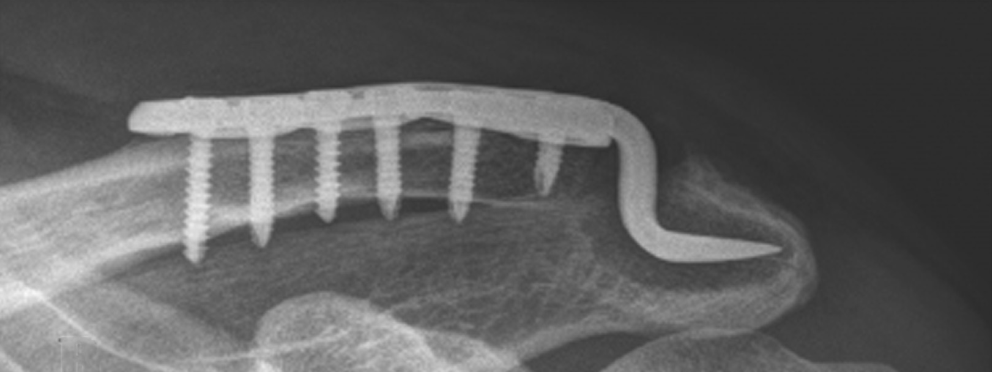

▲ 图示肩锁下骨溶解影像。(图源:10.1016/j.jse.2024.09.027)

钩钢板对肩锁关节脱位的固定,完全依靠于钩对肩峰的压力。研究表明,42-45%的钩钢板固定肩锁关节脱位病例会出现肩峰下骨溶解,钩与肩峰的匹配不良、II/III型肩峰或过度活动会增加骨溶解的发生率。

肩峰下骨溶解导致的肩部慢性疼痛,肩关节外展受限,是钩钢板固定后内植物取出甚至内植物失效的最主要原因。为了在医源上尽可能避免肩峰下骨溶解,对钩钢板的最佳放置位置研究,应运而生。